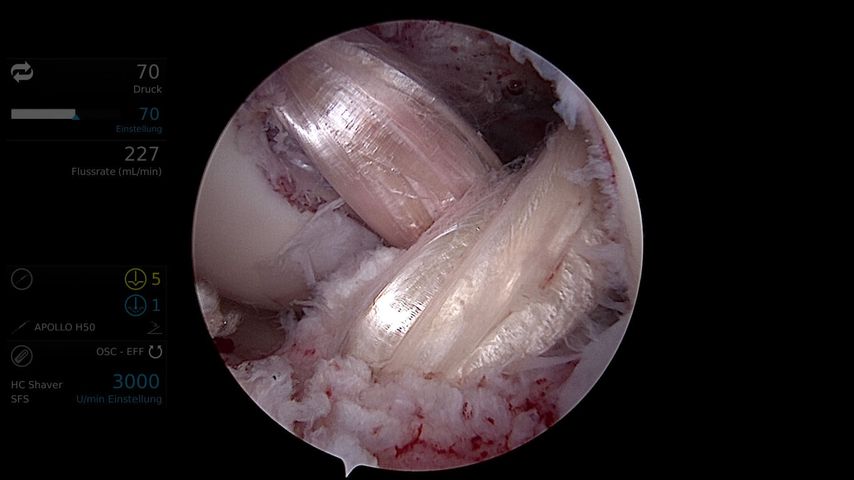

In der Regel wird bei multiligamentären Kniegelenksverletzungen zweizeitig vorgegangen. Hierbei werden primär, innerhalb von 2 Wochen, der mediale und der laterale Bandkomplex (periphere Pfeiler) und sekundär nach ca. 6–8 Wochen das VKB und HKB mittels Auto- oder Allograft rekonstruiert (Abb.3, 4).12

Aufgrund neuer chirurgischer Techniken und Implantate erfährt die Sehnenrefixation eine Renaissance. Durch zusätzliche Augmentation der Refixationen mit einem Fiber-Tape („ligament bracing“) kann die Primärstabilität erhöht werden. Das Fiber-Tape fungiert als eine Art Sicherheitsgurt, bis das native Band wieder ossär integriert ist. Frosch et al.konnten mit einer primären Refixation und zusätzlichem „ligament bracing“ ähnlich gute Ergebnisse wie bei einer Rekonstruktion erzielen.15